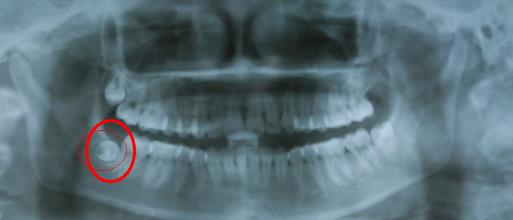

4、複雜牙齒拔除(包括智齒):特別是阻生牙、埋伏牙,位置不好,一般需要的時間要多很多,而且如果**不能很好的配合,拔牙難度就會(hui) 很大。所以價(jia) 格也是較貴的,一般在七八百元到兩(liang) 三千元不等。